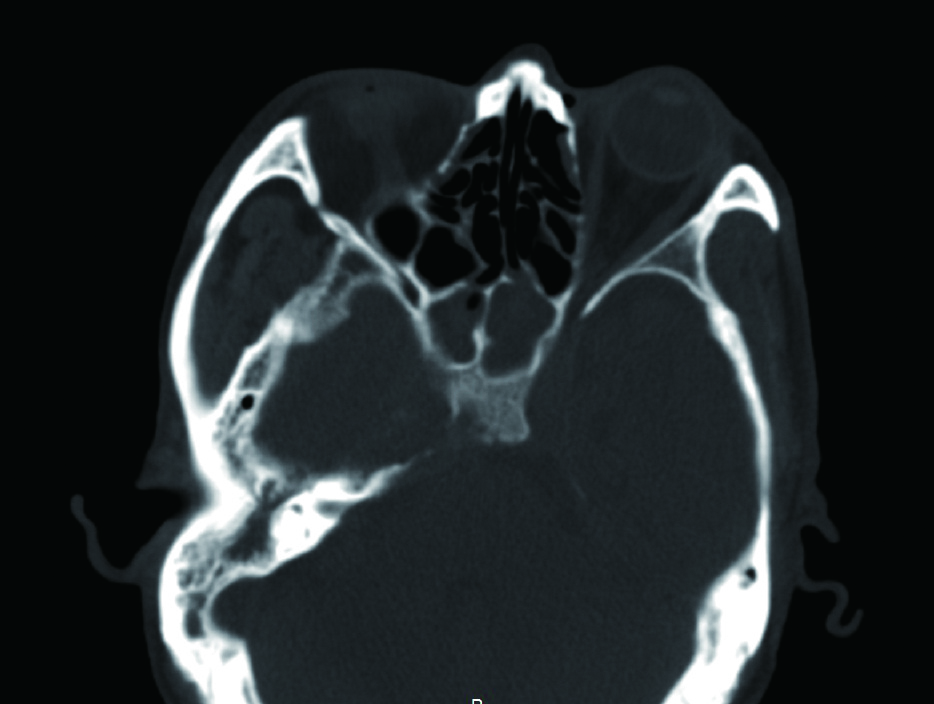

1 资料与方法病例1,患者男性,66岁,因头痛3周,复视1周入院。患者3周前起右侧太阳穴针刺样疼痛,影响睡眠。2周前出现咽痛鼻塞流涕及双耳听力下降,伴有右侧额部皮肤红疹,上述症状在当地医院治疗后减轻。1周前出现复视,当地医院治疗后症状无好转,诊断:颅内感染,多颅神经麻痹转来本院急诊。查体:神清,面部可见散在淡色丘疹,以右侧前额为主,右眼外展受限,面部痛触觉无殊,四肢肌力5级,病理反射阴性。脑脊液生化常规示:潘氏试验阳性,有核细胞970/μL;血沉28.00 mm/h,C反应蛋白14.1 mg/L。增强头颅MR提示两侧海绵窦增粗增宽,考虑炎症,并见双侧筛窦上颌窦蝶窦炎(图 1)。予头孢曲松钠2.0 g静脉注射抗感染治疗。治疗2周后头痛明显减轻,但复视症状无好转。复查血常规正常,C反应蛋白正常范围,血沉28.00 mm/h,脑脊液生化及常规正常范围。复查头颅增强MR提示病变范围较前无缩小。鼻窦CT提示双侧蝶窦炎症较前加重(图 2)。建议患者行鼻内镜下蝶窦手术。患者自觉症状减轻拒绝手术,要求出院。出院后在外院继续头孢曲松钠抗感染治疗。治疗10 d后因头痛复视症状无改善,并出现面颊部感觉减退再次入院。入院后查血常规,C反应蛋白正常,血沉28.00 mm/h,脑脊液潘氏试验阳性,细胞数量继续减少至60/μL。继续抗感染治疗。再次头颅MR及鼻窦CT复查提示海绵窦及蝶窦内病变较前范围增大(图 3),经多学科讨论,转本科行视频内镜下双侧蝶窦开放术。术后第三天鼻腔填塞物完全抽除后头痛症状明显缓解,术后6 d出院,头痛症状消失,复视仍存,出院后继续抗感染治疗,定期门诊复诊,术后6个月,复视症状消失。

| 图 2 左侧蝶窦密度增高影,右侧窦内密度增高影,窦内含气 |